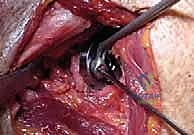

FIG 1 • A,B. Characteristic findings of cuff tear arthropathy, including superior displacement of the humeral head, “femoralization” of the proximal humerus, and “acetabularization” of the coracoacromial arch. In such a case, a conventional hemiarthroplasty, possibly using a special cuff tear arthropathy (CTA) head, may be considered.

* Anterosuperior escape: This is an exaggerated form of superior instability, occurring when the coracoacromial arch is compromised. The humeral head translates anteriorly and superiorly out of the glenoid.

FIG 1 • C,D. Anterosuperior escape of the humeral head resulting from surgical compromise of the coracoacromial arch. In such a case, a conventional arthroplasty will not provide stability, and a Delta (DePuy, Warsaw, IN) or reverse prosthesis may be considered. (Copyright Steven B. Lippitt, MD.)